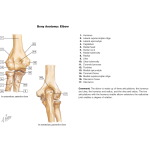

Bones of Elbow

Bones of Elbow

Labeled - Cleland Ortho Clinical Exam 1E